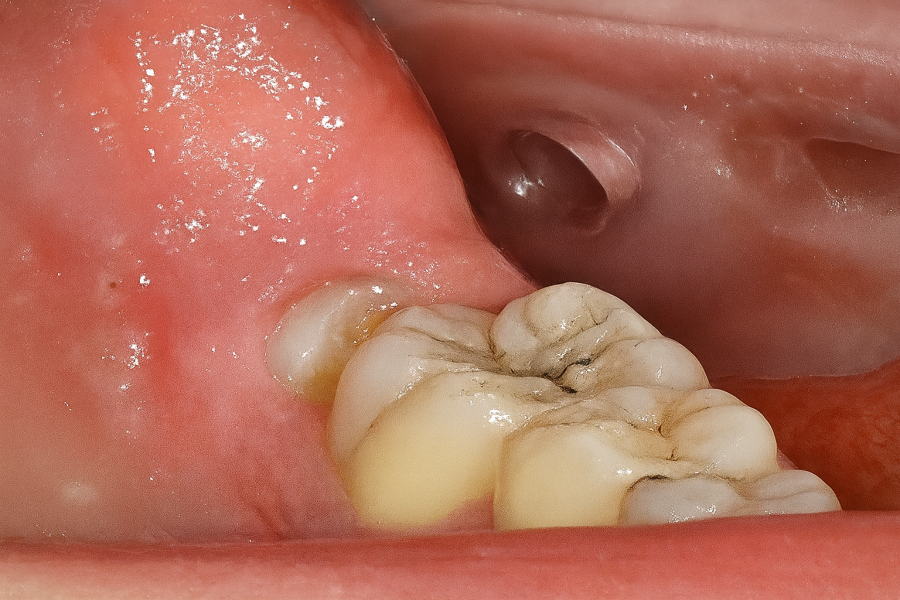

Métodos: Se presenta el caso clínico de un paciente varón de 18 años en el que, tras la realización de una CBCT de la arcada mandibular, se observó la retención de los segundos molares mandibulares permanentes junto con los terceros molares mandibulares.

Clínicamente la impactación de los 2M puede dar lugar a diversas complicaciones locales, entre las que se incluyen la aparición de lesiones quísticas, procesos infecciosos como la pericoronaritis o los abscesos, así como la sobreerupción de dientes antagonistas. Además, esta condición puede favorecer la aparición de patologías en los dientes adyacentes, tales como reabsorción radicular, caries, alteraciones periodontales, repercusiones estéticas y funcionales, incluyendo dificultades masticatorias7.